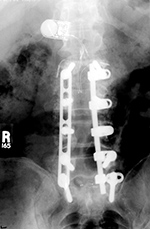

| Vertebral compression fracture treated by expandable corpectomy device |

Interbody vertebral cages |

| There are also bilateral pedicle screws and connecting rods above and below the level of the fracture. |

The cages are at L1-2 with bilateral pedicle screws and rods going from L1 to L3 for degenerative lumbar spine disease. |